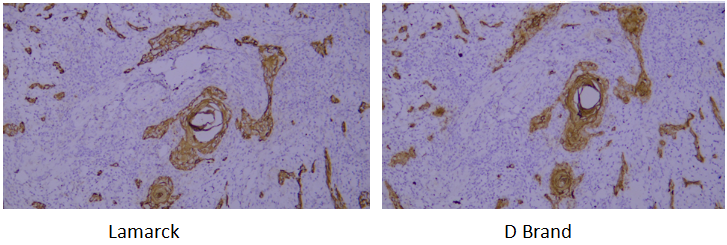

A verification system is established based on the strict requirements of clinical pathological testing. It not only conducts multi-dimensional checks on core indicators of purified antibodies (such as purity, isotype, and IHC performance) to ensure stable and uniform antibody performance, but also verifies via parallel control experiments with well-known international pathological antibody brands. Through horizontal comparison of IHC results on human tissue samples, the detection effect is confirmed to be consistent with and even superior to top international standards.

Target: CD31

Tissue: human liver